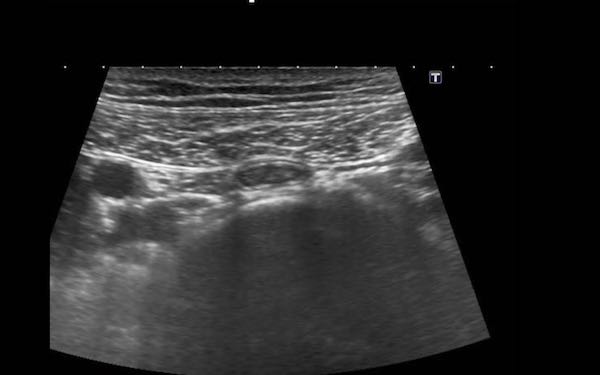

Đây là hình ảnh siêu âm của một trẻ 2 tuổi bị lồng ruột hồi manh tràng từng đợt, được khám trong khoảng thời gian giữa các cơn.

Hồi tràng với nhiều mảng Peyer sa vào manh tràng.

Hình ảnh siêu âm kinh điển của lồng ruột hồi-manh tràng ở hai trẻ khác nhau.

Trong cả hai trường hợp, đoạn hồi tràng bị lồng được định vị không đối xứng bên trong ống lồng ngoài, do mạc treo ruột tăng âm có chứa mỡ, bám vào hồi tràng và đi theo hồi tràng khi bị kéo vào trong.

Trong mạc treo, siêu âm cho thấy một hạch bạch huyết mạc treo (hbh) phóng đại ở cả hai.

Các hạch này phì đại như một phần của tình trạng tăng sản hạch bạch huyết toàn thân và khônghu trú trong lòng hồi tràng.

Do đó đây không phải là điểm dẫn đầu nguyên phát. Ở bệnh nhân bên phải, ruột thừa (mũi tên) cũng bị kéo vào trong.

Lưu ý cấu trúc đa lớp của thành bụng phía trước của phức hợp lồng ruột, đại diện cho ba lớp thành ruột bị gấp lại.